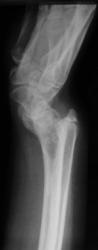

Девочка 14 лет. Ранее за помощью не обращались. Только в этом возрасте родителей и саму пациентку начала беспокоить деформация предплечий.

Рентгенологическая классика для болезни Маделунга:

1. Укорочение лучевой кости.

2. «Скошенность» суставной поверхности дистального эпифиза лучевой кости в ладонную и локтевую сторону, что «симулирует» визуально подвывих костей запястья.

3. «Нависание» полулунной кости над ладонным краем дистального эпифиза лучевой кости.

4. Высота дистального эпифиза по лучевой стороне превосходит его высоту по локтевой стороне.

5. В результате раннего закрытия ростковой зоны по локтевой и ладонной стороне, формируется ладонный и локтевой наклон суставной поверхности.

6. Деформация и изменение расположения проксимального ряда костей запястья, по форме, напоминающей «клин», вершиной которого является полулунная кость.

7. Головка локтевой кости находится в положении «вывиха» и смещена в «тыльном» направлении, по отношению к лучезапястному суставу.